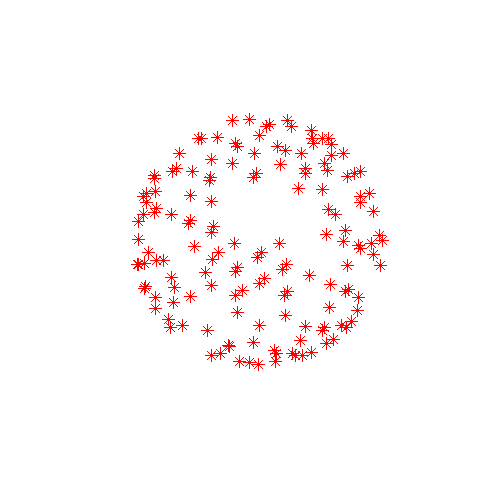

| Data sampled on the half-sphere | Data sampled on the whole-sphere |

![]() |

| The red dots corresponds to sample points on the diffusion sphere, *i.e.* they can be thought of as endpoints of a set of arrows starting at the origin and representing the diffusion gradients. The whole sphere on the right has been created by negating a subset of the vectors on the left. Hence they are identical w.r.t. sampling the diffusion signal. | |